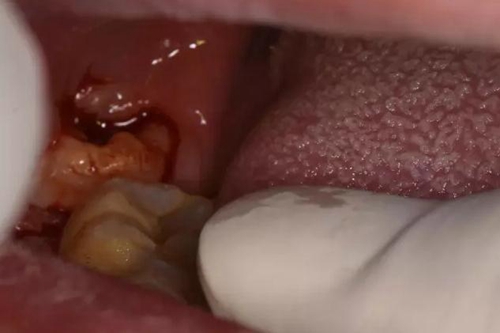

圖3.口內(nèi)檢查:48垂直阻生、有盲袋、牙冠萌出3/4,36、37牙齒健康。